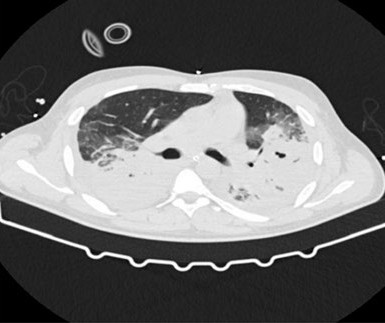

The Panton Valentine Leukocidin (PVL), produced by Staphylococcus aureus (SA) strains, is a potent virulence factor associated with severe invasive disease. One of the most serious clinical presentations, necrotizing pneumonia, frequently presents in previously healthy young individuals. However, PVL presence is not routinely tested, and strong clinical suspicion should guide clinicians, since appropriate antimicrobial therapy, with the association of agents capable of PVL production inhibition, is crucial. The authors hereby present a case report of a young, previously healthy adult male, admitted to an Intensive Care Unit due to acute hypoxemic respiratory failure. The patient evolved with a severe necrotizing pneumonia due to methicillin-susceptible Staphylococcus aureus (MSSA) and Klebsiella pneumoniae requiring two beta-lactam antibiotic therapy and invasive mechanical ventilation. Persistent clinical deterioration led to the clinical suspicion of an underlying PVL-producing SA strain. The patient evolved favourably with the association of linezolid and laboratory testing posteriorly confirmed PVL-producing MSSA.